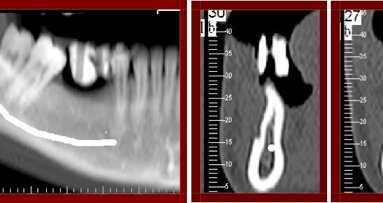

El tratamiento propuesto fue injerto de hueso en el maxilar superior y levantamiento bilateral de los senos maxilares con hueso homogéneo y obtención de tejido músculo-esquelético en el Hospital Clínico de la Universidad de Paraná. La característica morfo-esquelética del anillo óseo era córtico-medular, retirado de la tibia (Foto 3). El bloque era limpio y particulado (Particulador KOPP), del cual se obtuvieron dos tamaños de partículas a las que posteriormente se atornilló la prótesis de porcelana sobre minipilares R Kopp, con torque de 32 Newtons y ajustes oclusales (Foto 15).

Seis meses se indicó una placa panorámica para verificar los resultados (Foto 16). La radiografía (Foto 17) muestra el grosor del reborde durante el injerto y la Foto 18 la situación clínica despúes de abrir los implantes osteointegrados.